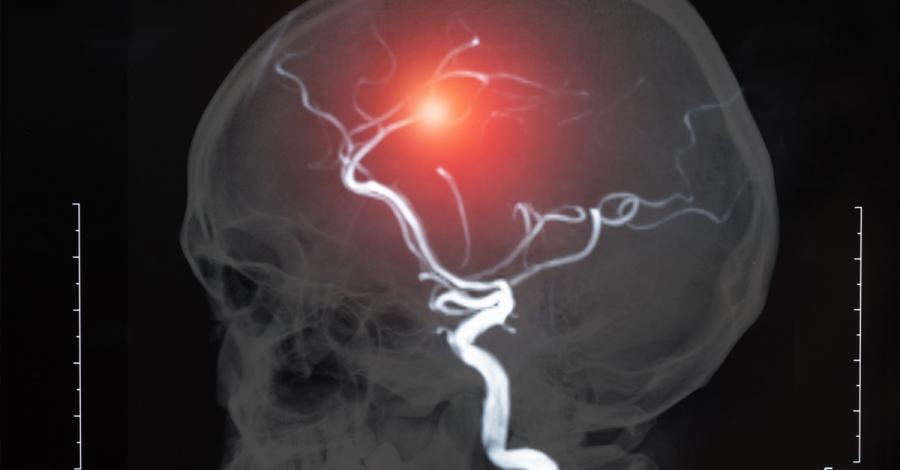

Учени създадоха „жива“ аневризма от кръв и човешки мозъчни клетки

Мозъчните аневризми са нещо кошмарно – кръвоносен съд във вашия мозък, който тихомълком се издува и един ден може да се спука и да предизвика животозастрашаващи усложнения.

Илюстрация на 3D принтирана аневризма (а) и структура на съдовете в аневризмата (b). Източник: Kang et al., Biofabrication, 2020